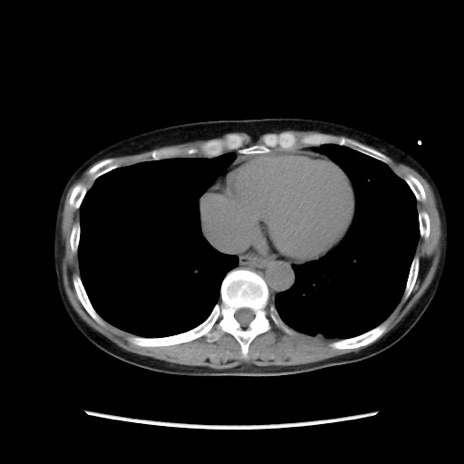

症例32(横断像)

【症例】40歳代 女性

【主訴】上腹部痛、嘔気・嘔吐

【現病歴】約9時間前頃から急に上腹部痛、嘔気、嘔吐が出現。改善しないため救急要請。

【既往歴】子宮頚癌(広汎子宮全摘術、放射線療法)、腸閉塞

【身体所見】腹部:平坦、軟、腸雑音亢進、上腹部を中心に腹部全体に圧痛あり。

【データ】WBC 8400、CRP 0.03